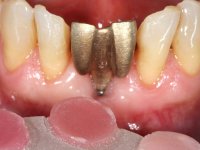

Being an esthetic area it was decided to do an immediate splint of the crowns 41 and 31 to the adjacent teeth with a metalic mesh bonded in the lingual surface.

• Extraction of teeth 41 and 31 keeping the crowns of the same teeth as a provisional situation.

Splinting of teeth 41 and 31 to the adjacente teeth with a metallic mesh allowed us to temporarily resolve the esthetic situation and simultaneously avoid the use of a removable prosthesis, during the healing of the sockets and also during the osteo-integration phase of the dental implant.